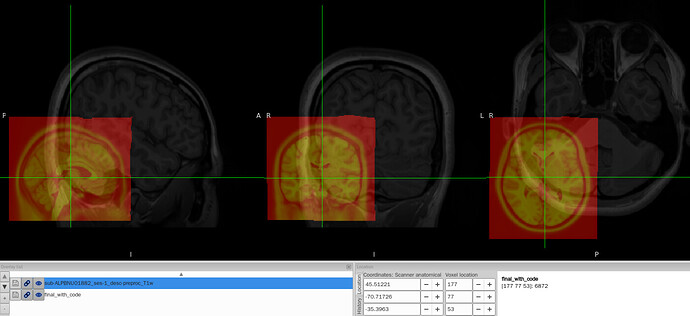

I tried to convert the ANTs-format warp (from-MNI152NLin2009cAsym_to-T1w_mode-image_xfm.h5) generated by fMRIPrep into FSL format (from-MNI152NLin2009cAsym_to-T1w_mode-image_xfm_fsl.nii.gz) using c3d affine tool, so that I could use it later in pyAFQ for tractography. The conversion itself works fine, but once I add intent code to FSL xfm header(intent code 2006), the warp seems to be damaged. To be specific, the FSL warp applied to MNI template shifted to the lower-left corner and it no longer aligns with the T1w image.